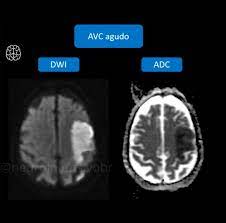

Entenda como essa técnica detecta precocemente AVCs, tumores e lesões cerebrais.